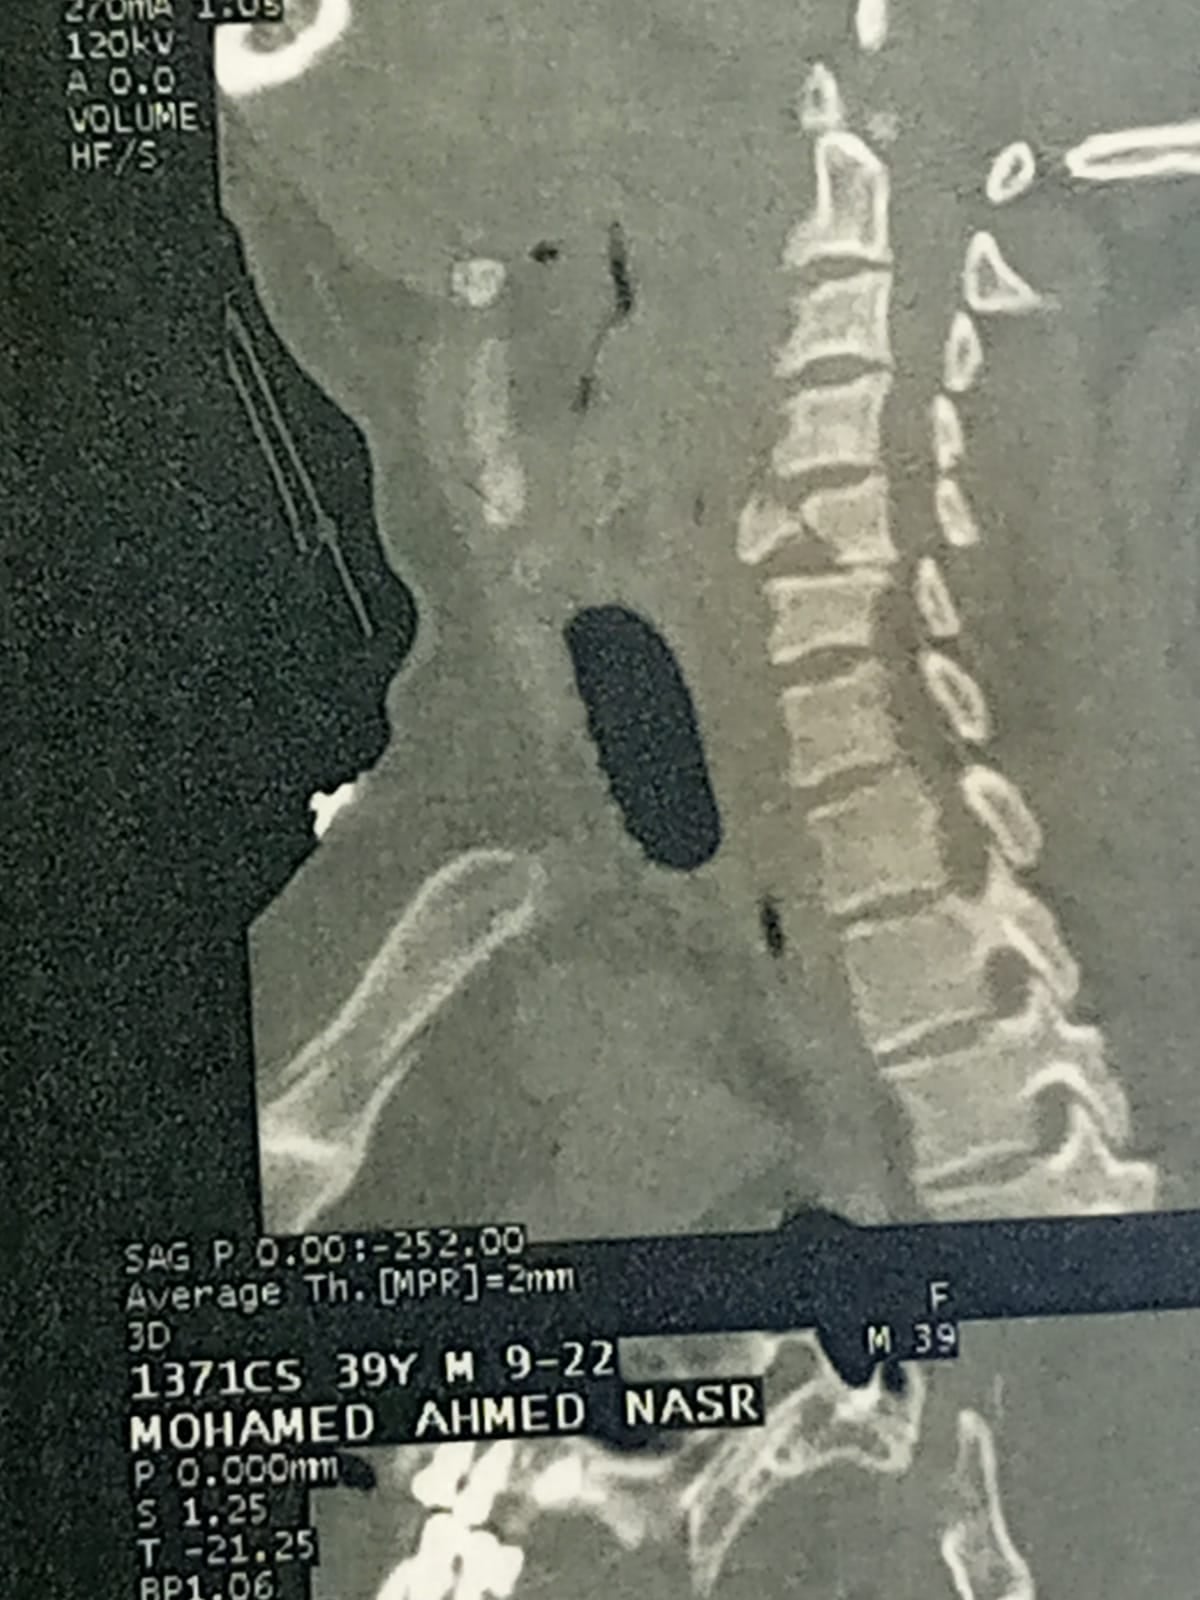

وذكرت مديرية الشؤون الصحية أن مستشفى برج العرب المركزي، الكائنة بغربي الإسكندرية، استقبلت اليوم، مريض، يبلغ من العمر، 40 عامًا، من أحد المستشفيات الخاصة، بتشخيص يشير إلى أن الإصابة عبارة عن كسر متفتت في الفقرة العنقية الخامسة.

وشهدت الجراحة استئصال الفقرة الخامسة «المفتتة» ووضع دعامة عنقية وتثبيتها بواسطة شريحة ومسامير وتوسيع القناة العصبية.